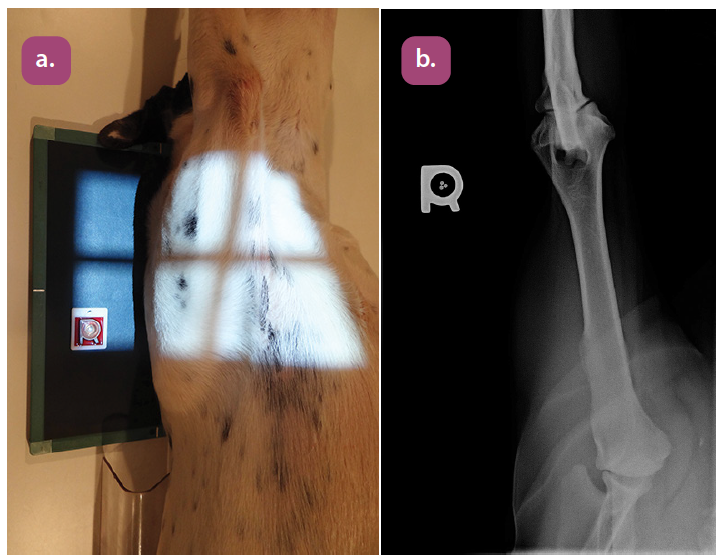

mediolateral projection of the tibia

caudocranial projection of the tibia and fibula